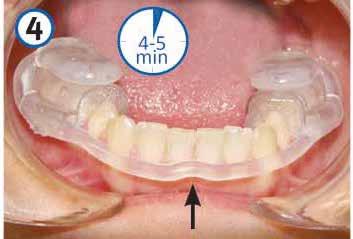

A fogszabályozás aktív fázisa után minden kezelésnél a retenció, a passzív helyben tartó fázis a kezelési eredmény megtartására rendkívül fontos!

Az Essix retainerek, az egy fogívre kiterjedő mélyhúzott sínek, valamint a felső és alsó frontfogakra orálisan ragasztott fix retainerek mellett, a harapás sagittális rögzítésében elengedhetetlen szerepe van az ún. Pitts Izom Tréning Splint-nek, amelybe a páciens élharapásban összeharap, így az megakadályozza az alsó fogsor visszamozdulását a disztálharapásos helyzetbe (13. kép)